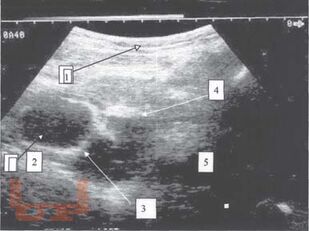

Диагностика и лечение опухолей и опухолевидных образований яичников у девочек и подростков является актуальной проблемой. Совершенство методов диагностики при данной патологии, хорошо зарекомендовавших себя во многих областях медицины, способствует внедрению их в клинику детской гинекологии, онкогематологии, детской хирургии.

Разнообразие средств диагностики, отличающихся по физическим данным и разрешающим способностям, а также по стоимости аппаратуры и самих исследований, часто ставит врача перед сложной проблемой определения необходимого минимума применяемых методов, последовательностью их выполнения и интегрирования результатов разных исследований в единую диагностическую концепцию.